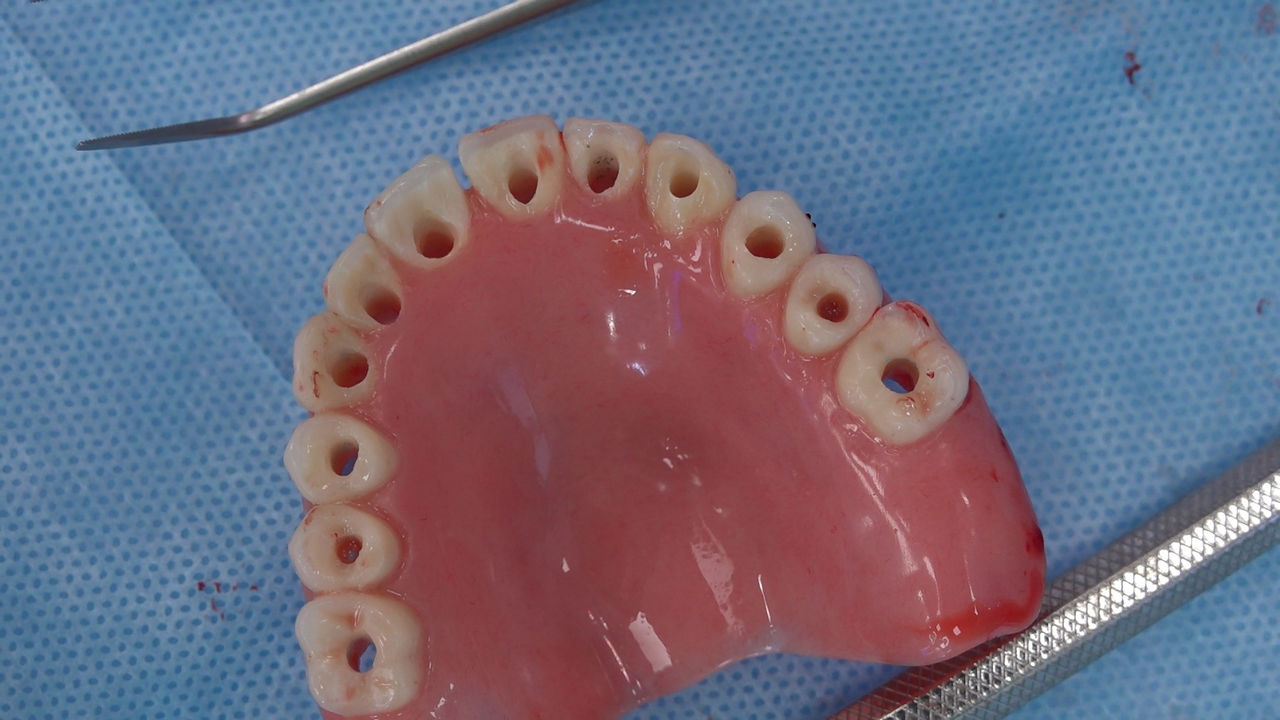

Practiculum Implantologii to szkolenie dla adeptów implantologii zorientowane na praktyczne opanowanie procedur zabiegowych i wprowadzenie implantologii do własnej praktyki. Dla Kursantów Grupy A, X Sezonu, 9 Sesja stanowiła ostateczny sprawdzian umiejętności zabiegowych zdobytych podczas procedur wykonywanych w trakcie szkolenia pod kierunkiem dr n.med. Violetty Szycik i dr Małgorzaty Piotrowskiej. Zobacz więcej na: www.practiculum.pl